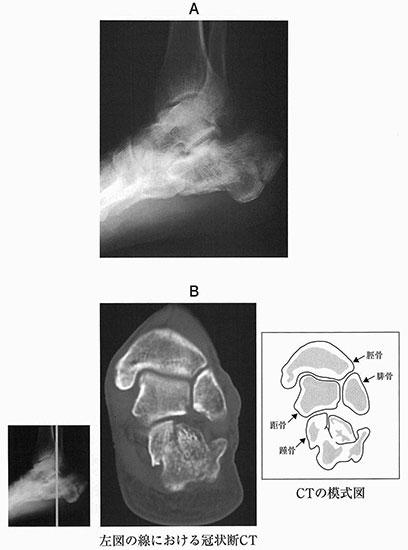

55歳の男性。トラックの荷台(2 m)から転落して受傷した。来院時の足関節エックス線単純写真(A)及び冠状断CTとCTの模式図(B)を別に示す。保存的に加療したとき、今後最も起こりやすい合併症はどれか。